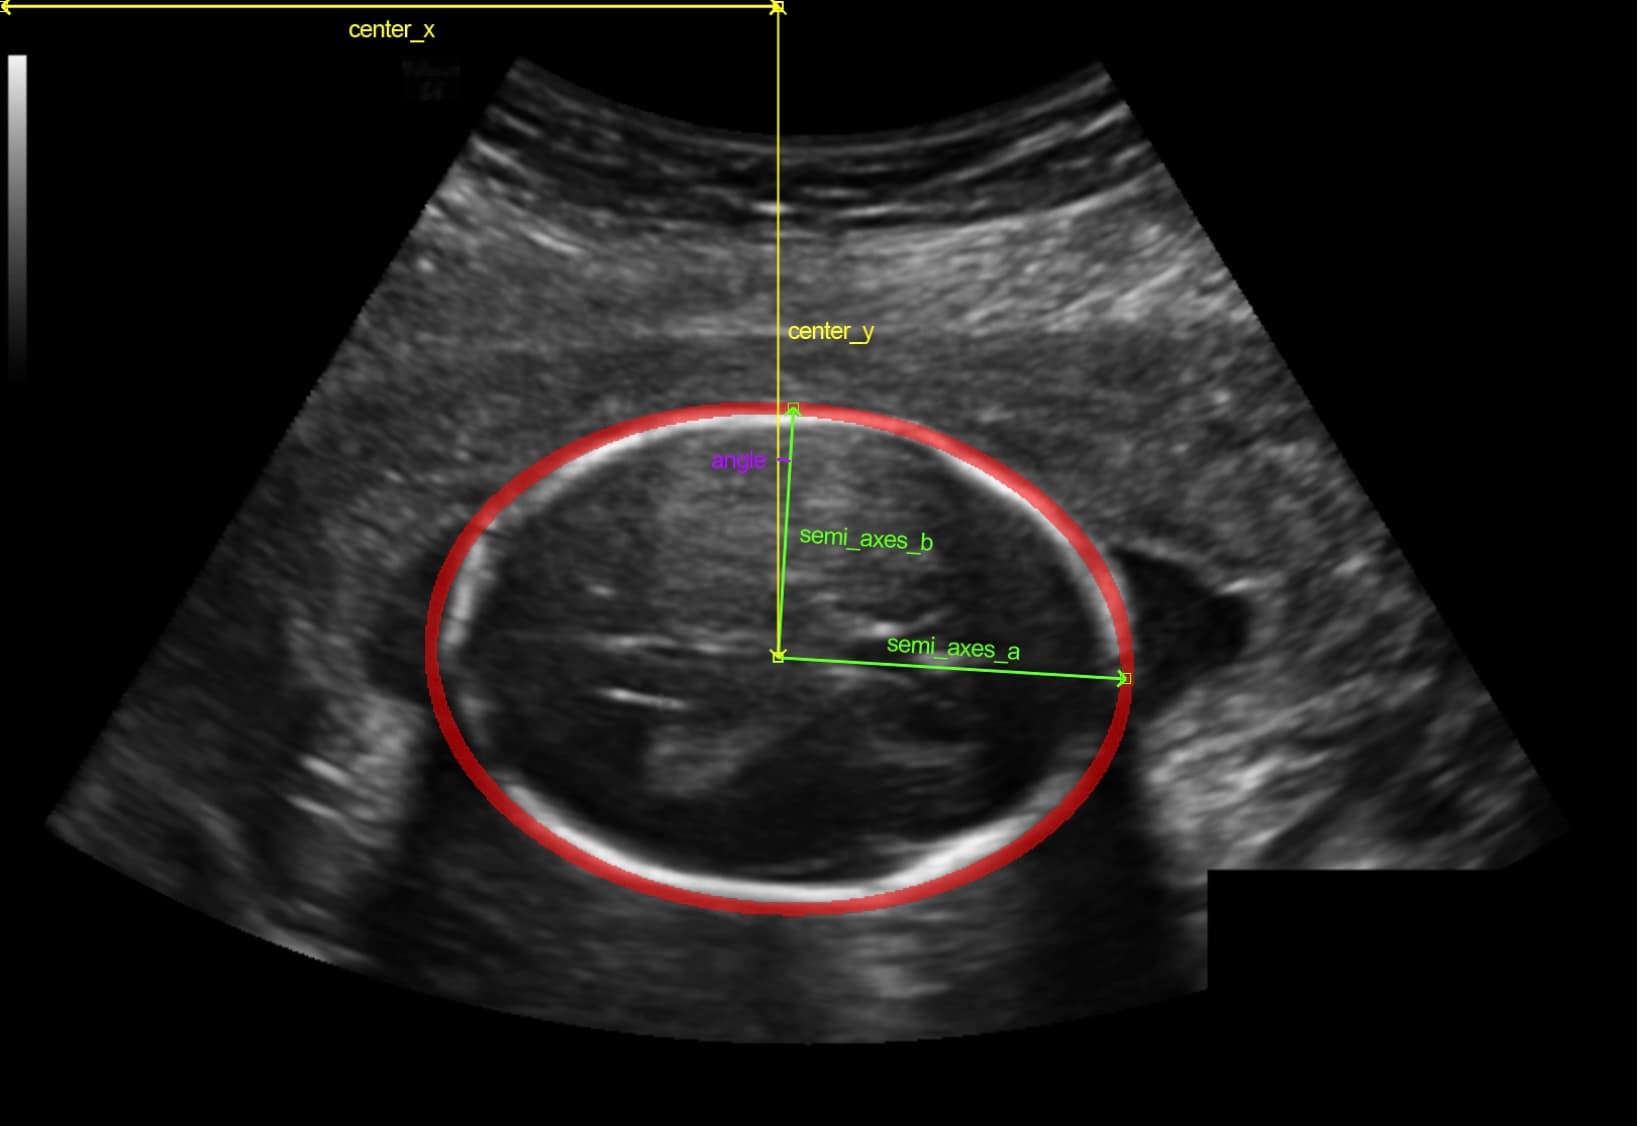

Best in World Model for Medical Imaging

Best ML model performance out of 2,212 entries.